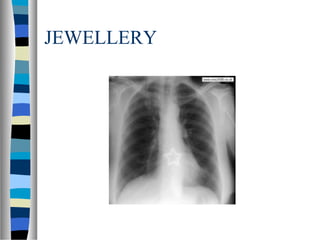

JEWELLERY